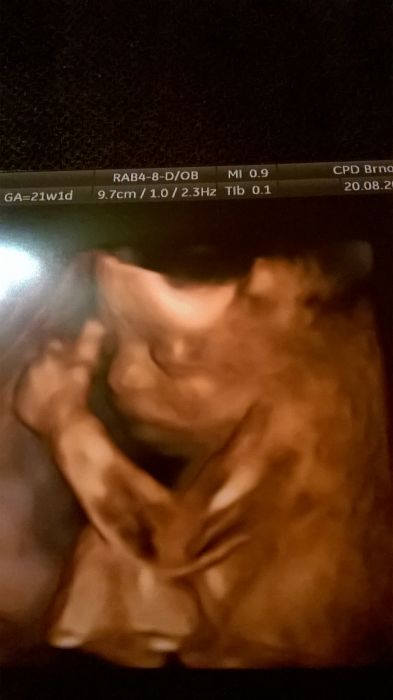

Ahoj Vercus, fotečka krásná, můžu závidět, my nemáme